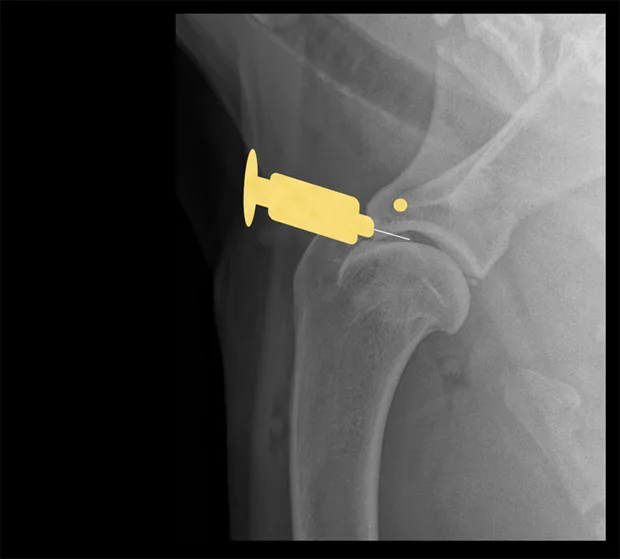

Hip

Place the patient in lateral recumbency with the hip upward in slight abduction and slight external rotation. Insert a 22- or 20-gauge, 3-inch spinal needle just dorsal to the greater trochanter, and enter the joint in a lateral-to-medial direction. For a ventral approach, insert the needle just caudal to the pectineus muscle over the hip joint, directed at a 45° angle in a craniodorsal direction. Some resistance may be felt as the needle is passed through the ventral joint. Ultrasound guidance is helpful but not essential.

Lateral view of pelvis. Insert the needle at the proximal extent of the greater trochanter into the hip joint in a lateral-to-medial direction.